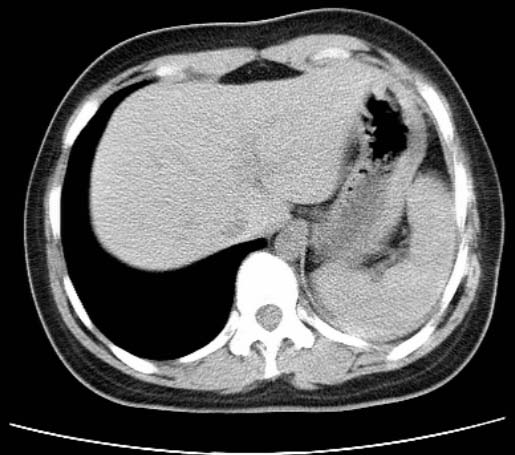

女  20岁。一月前咳血,诊“肺结核”抗痨治疗一月后,咳血停止,现复查。病人精神好。前后ct片对比未见明显变化。既往体检“正常”

1)考虑左肺结核并肺不张、支气管扩张。2)纵隔疝。

考虑左肺结核,左肺毁损,纵膈左偏,既往体检正常不可靠,tb一个月也不会这个样子的,有钙化,应该病程较长,冰冻三尺非一日之寒!

左肺发育不全。

考虑左肺结核,左肺毁损,纵膈左偏,既往体检正常不可靠,tb一个月也不会这个样子的,有钙化,应该病程较长,冰冻三尺非一日之寒

结核,左肺毁损。